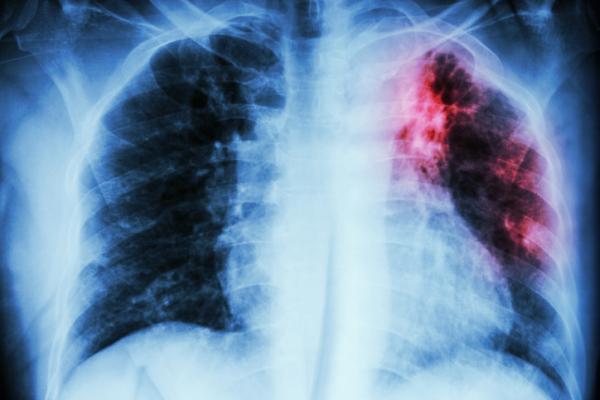

December 7, 2020 — An analysis of lung tissues from patients with different types of pulmonary fibrosis - including cases triggered by COVID-19 - has revealed a promising molecular target to ameliorate the chronic and irreversible disease. Experiments in mouse models of lung fibrosis showed that administering blockers of an epigenetic regulator called MBD2 via intratracheal inhalation protected the mice against fibrotic lung injury, highlighting a potential viable therapy. A poor understanding of what causes pulmonary fibrosis has greatly hindered the development of treatments, and to this day, no effective therapy is available other than lung transplantation. To tackle this limitation, Yi Wang and colleagues studied lung samples from patients with pulmonary fibrosis triggered by one of three causes: SARS-CoV-2 infection, systemic sclerosis-associated interstitial lung disease, or an unknown factor. The researchers also studied mouse models of pulmonary fibrosis, which they induced in the animals by administering the compound bleomycin. All cases of pulmonary fibrosis, they found, were characterized by overexpression of MBD2. This activity localized in areas occupied by macrophages - known contributors to the development of pulmonary fibrosis. To investigate this further, the scientists depleted the Mbd2 gene in macrophages of mice, which protected the animals against pulmonary fibrosis, characterized by markedly reduced macrophage accumulation in the lung following administration of bleomycin. As well, direct administration of liposomes - established carriers of inhaled drugs - loaded with Mbd2 silencer RNA into the trachea of mice protected them from lung injuries and fibrosis. Since MBD2 itself does not affect the essential epigenetic process of DNA methylation, inhibiting the molecule could prove to be a safe way to treat pulmonary fibrosis. However, future studies will first need to assess the impact of altered MBD2 expression in other types of cells relevant to pulmonary fibrosis, the authors say.